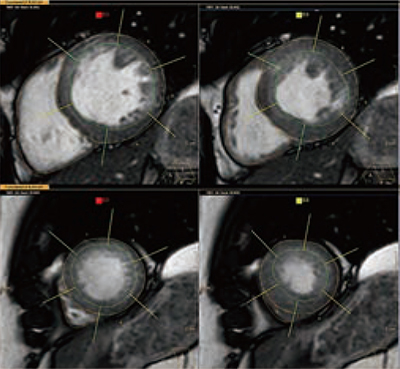

Cardiac MR Analysisは,心機能解析・遅延造影の解析アプリケーションである。一般的な心機能解析,Bull’s-eye(wall motion,wall thickness,wall thickening),volume over time graphから拡張機能の評価ができるなど,多くの解析が可能である(表1)。心臓MRIは時間がかかる検査とされてきた。近年はフィリップスのMRI高速撮像技術「Compressed SENSE」や「SmartSpeed」により,撮像時間の大幅な短縮が可能となったが,解析には多くの時間がかかることが負担となっている。心機能解析のFunctional LV & RV解析では,AI技術によりLV(左心室),RV(右心室)の内腔,外腔の自動トレースを実現し,解析時間を大幅に短縮できるようになった。さらに,事前に設定することでデータ受信後にバックグラウンドで自動解析が可能であり,アプリケーションを起動すると,解析が終了している状態から始めることができる。解析者はED(拡張期)/ES(収縮期)フェーズと心室の自動トレースの確認作業のみで解析結果が得られ,PACSやレポートに転送できる(図1)。それにより,従来,約20分を要した心機能解析を5分以内で終えることができる。また,トレース作業にかかる時間や精度は解析者の経験値によって大きく差が出るが,自動トレースになることで個人差も低減できる。これまで時間に追われ検査と解析を同時進行していたユーザーも,検査に集中できるようになり,検査を受ける側にとっても優しい環境を提供できる。

図1 ED(拡張期)とES(収縮期)のAutomatic segmentationを利用したLV,RVトレース